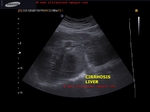

cirrhosis-liver-3D-ultrasound

3D ultrasound with surface rendering shows the Rt. lobe of liver-

-contracted shrunken liver s/o end stage cirrhosis

- nodular cobblestone surface of liver on 3D accentuated by surrounding ascitic fluid

- splenomegaly with splenic varices s/o portal hypertension